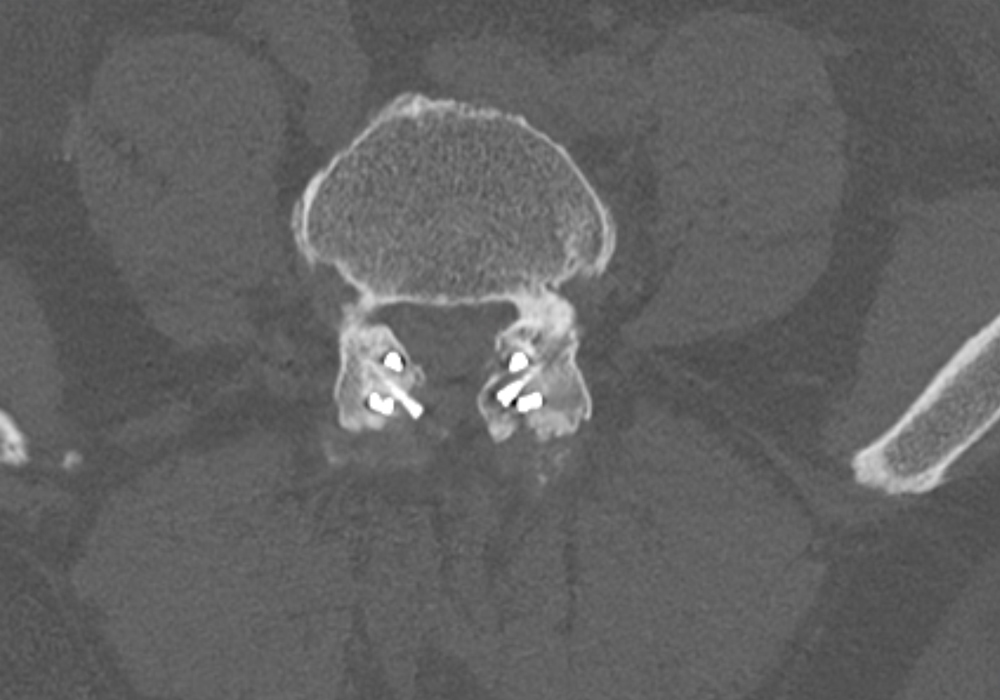

Preop.

2-year Postop